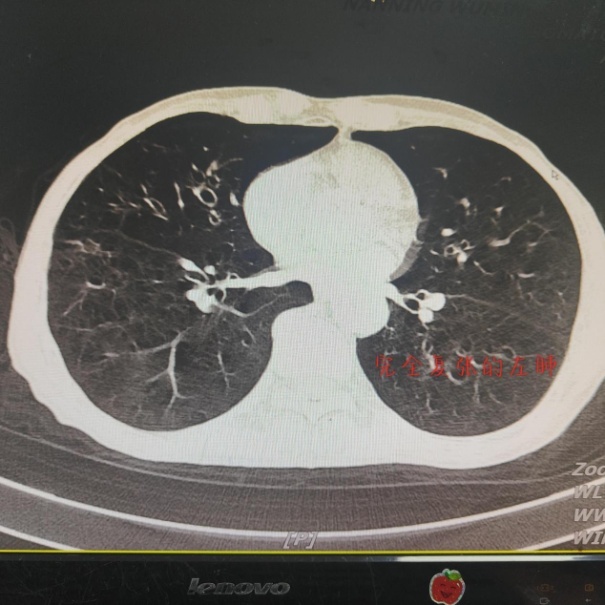

入院后,内科医师给予经鼻导管吸氧、胸腔闭式引流、抗感染、化痰、平喘等治疗,但症状无明显好转,胸口闷,呼吸急促等不适仍困扰着邓大爷。考虑到高浓度吸氧可加快胸腔内气体的吸收,医生决定予以经鼻高流量湿化氧疗。

邓大爷接受经鼻高流量湿化氧疗